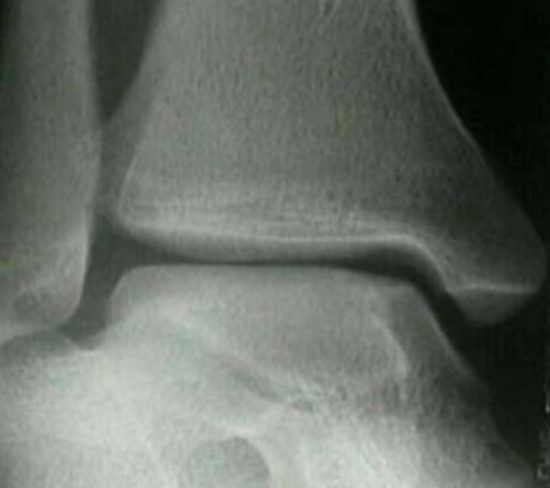

Initial imaging should include anteroposterior (AP), medial oblique (MO), and lateral radiographs of the ankle to evaluate for a defect. It is imperative the treating physician appreciate the mechanism of injury and thoroughly evaluate the radiographs personally for a lesion on the talus. If a more detailed view of the OCD is warranted, an MRI can be obtained. MRI is considered the gold standard in imaging for juvenile OCD of the talus and is found to be highly accurate, with a sensitivity of 92% and specificity of 50%. CT scans may also provide a useful better evaluation of the subchondral bone and could assist with surgical planning.10